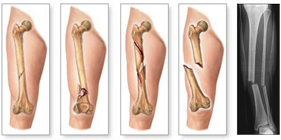

Questo tipo di fratture che, quindi, necessitano di una fissazione chirurgica verranno rese stabili da mezzi di sintesi diversi; si parla in questo caso di osteosintesi.

Durante l’intervento di osteosintesi i frammenti ossei vengono riallineati con appositi strumentari e vengono fissati con fili metallici, viti, placche, chiodi, fissatori esterni, ecc.

Ognuno di essi presenta specifiche peculiarità che ne determinano vantaggi e svantaggi. La scelta del mezzo di sintesi viene fatta dal Chirurgo in base a molteplici considerazioni (tipo di frattura, condizioni del paziente, qualità dell’osso). La maggior parte dei mezzi di sintesi è costituita da leghe metalliche, generalmente il titanio, che sono perfettamente biocompatibili. Essi possono, pertanto, rimanere in situ senza creare particolari problemi. Nei pazienti giovani o nel caso in cui i mezzi di sintesi diano fastidio perché troppo superficiali o perché determinano limitazione del movimento, si tende a rimuoverli dopo un tempo adeguato dalla guarigione (in genere dopo circa 18-24 mesi dalla frattura).